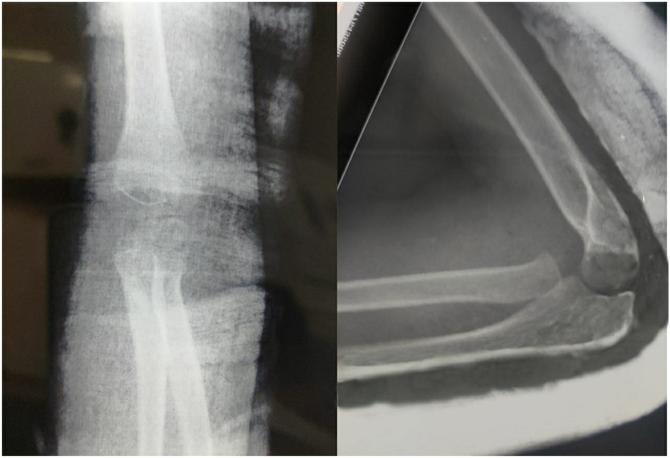

CASE

A 6-year-old female child presented to us with posterior elbow dislocation, PRUT and incomplete ulnar nerve palsy. A hematoma aspiration and reduction of the elbow joint were done with a hyper-supination manoeuvre to reverse the translocation. She was managed with an above-elbow cast for 4 weeks and showed good radiological and functional outcomes on subsequent follow-ups until 1 year.

近端桡尺关节脱位(PRUT)合并肘关节脱位且无骨折,是一种极其罕见的损伤。

病例

一名6岁女童因肘关节后脱位、PRUT和尺神经不完全麻痹前来就诊。进行了血肿抽吸及肘关节复位,并采用过度旋前手法来纠正脱位。她使用上臂石膏固定4周,在随后长达1年的随访中,影像学和功能恢复情况良好。